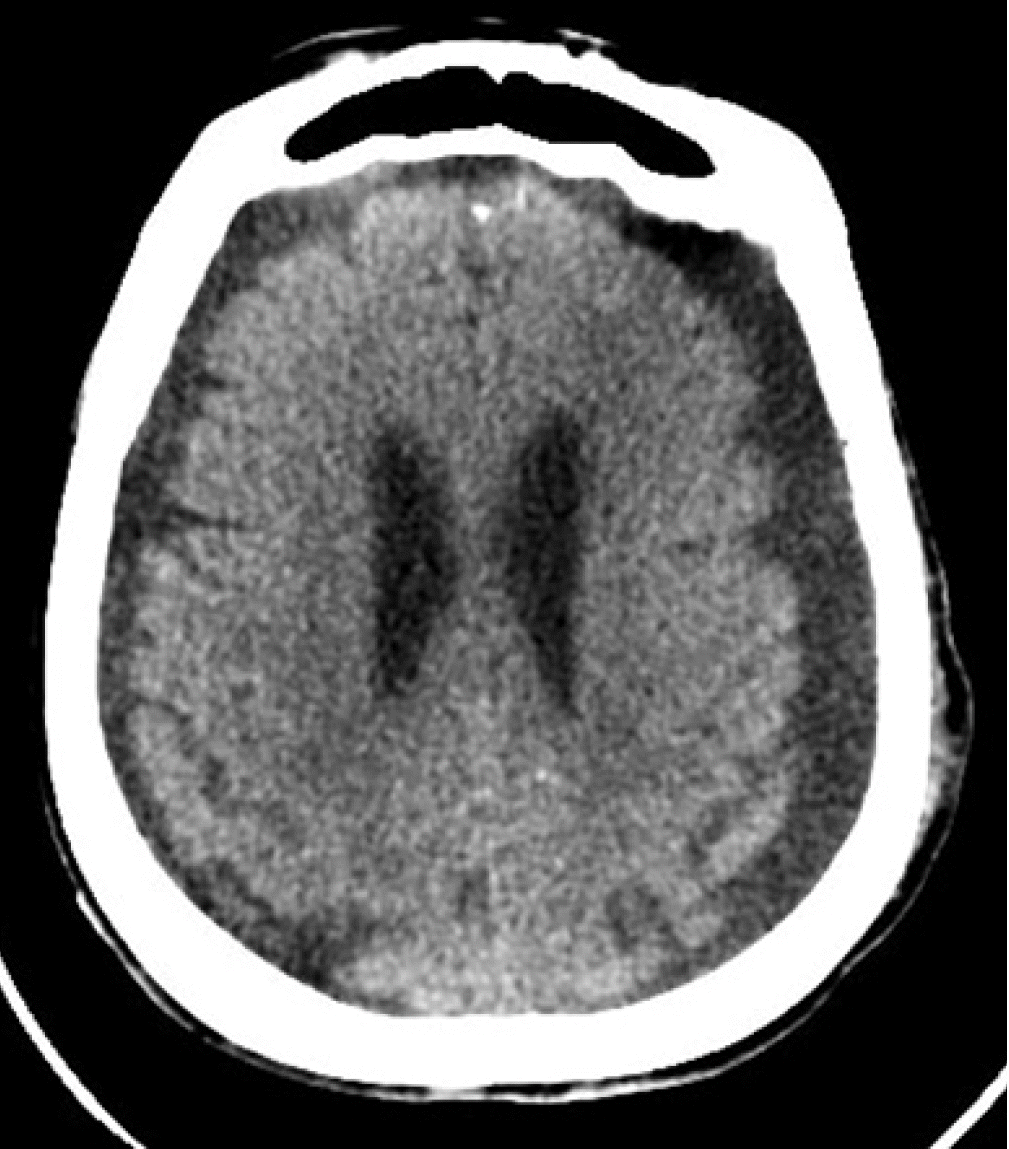

Our patient was an 84-year-old female with a past medical history of diabetes mellitus, hypertension, paroxysmal atrial fibrillation, and an old cerebrovascular event (left middle cerebral artery infarction) with no residual weakness. She was ambulatory with acceptable cardiorespiratory status for her age. Following a fall, she was admitted to our hospital with a left intertrochanteric femur fracture. On the next day, an orthopedic surgeon performed Gama nailing of the femur. The postoperative course was uneventful. On the 7th postoperative day; however, she developed right-sided hemiparesis and altered mental status. The Glasgow coma scale (GCS) was 10/15 (E4, V1, M5). Noncontrast computed tomography (NCCT) of the brain suggested bilateral cerebrospinal fluid (CSF) hygroma more strongly affecting the left side than the right side at the cerebral convexity (Figure 1). She was referred to a neurosurgeon and subsequently underwent a left parietal Burr hole and evacuation of CSF hygroma under general anesthesia. She was extubated in the postoperative period and remained in an intensive care unit (ICU) for neuro observation. Postoperatively, her GCS was 15/15 (E4, V5, M6), but she had persistent right-sided hemiparesis, which was similar to her preoperative state. Six hours postoperatively, she developed generalized tonic-clonic seizures, and her GCS dropped to 5/15 (E1, V1, M3). She underwent immediate intubation to secure her airway. She was sedated with a continuous infusion of fentanyl and midazolam, and she was connected to mechanical ventilation. She also received antiepileptic levetiracetam. Another NCCT of the brain revealed near-complete evacuation of the bilateral CSF hygroma and development of the classic “Mount Fuji” sign, indicating the formation of TPC (Figure 2). Her management included maintenance in a flat position in bed, 100% oxygen, sedation, an antiepileptic, and other brain-protective measures. She underwent immediately surgery, and a neurosurgeon performed left frontoparietal decompressive craniectomy under general anesthesia. Postoperatively, she was kept in the ICU under sedation. On the second postoperative day, a repeat NCCT of the brain showed near-complete resolution of the pneumocephalus. Her sedation was stopped, but her GCS did not improve beyond 9/15 (E4, V1, M4). On the 7th postoperative day, she underwent a tracheotomy for low GCS. Unfortunately, the patient developed other complications associated with her critical illness: ventilator-associated pneumonia, sepsis, acute kidney injury, and multi-organ failure. Finally, she succumbed to death on the 25th postoperative day. Because the patient was deceased, we obtained consent from her son for publication of this case report. This case report was approved by the head of the ICU of our hospital.

Pneumocephalus can be investigated by plain X-ray of the skull and computed tomography (CT) of the brain [5]. Although X-ray of the skull can detect a large pneumocephalus, it is seldom used with the advancement of CT; CT of the brain is the investigation of choice [9]. When pneumocephalus is detected on brain CT, the patient should be investigated for a skull base fracture or CSF leak [1]. Radiological signs described for diagnosis of pneumocephalus/TPC are the peaking sign, Mount Fuji sign, and air bubble sign [5,9]. The peaking sign is bilateral compression of the frontal lobes caused by trapped air in the subdural space. This sign demonstrates no separation of the frontal lobes and is more common in pneumocephalus than in TPC [5,9]. The Mount Fuji sign is bilateral compression and separation of the frontal lobes due to trapped subdural and interhemispheric space air. It is observed as non-attenuating collections formed between the two frontal lobes and is specific to TPC [5,9]. The air bubble sign is the presence of multiple air bubbles scattered around the cisterns. It is caused mainly by a tear in the arachnoid membrane and is more common in TPC [5,9].

In our case, the patient developed pneumocephalus by the “inverted soda bottle effect” after drainage of CSF, and she clinically presented with acute seizures and a decrease in GCS, which indicated increased ICP. Thus, it was concluded that she did not have simple postoperative pneumocephalus but TPC. The reported incidence of pneumocephalus after the evacuation of CSF or blood from subdural space is 2.5% [8]. In our case, TPC was confirmed by a brain CT that showed the “Mount Fuji” sign, which is specific to TPC [5,9]. We managed this patient by keeping her in the supine position to prevent further CSF leaks, and she was given 100% supplemental oxygen to hasten the removal of intracranial nitrogen (air). Some authors, like Heidari [10] have reported successful conservative management over neurosurgical decompression in a patient with a massive pneumocephalus. Options of neurosurgical decompression include needle decompression either blind or under radiological guidance through an existing burr hole or craniotomy [1], controlled decompression via a closed water-seal drainage system [11], ventriculostomy for air in the ventricle [8], emergency decompression by creating new cranial Burr holes [8], and decompressive craniectomy [8]. Individual performance, outcome, or superiority of one procedure over those of another are not well studied in the reported medical literature, but there is a theoretical risk of intracranial infection with needle/drain decompression [12]. The choice of neurosurgical decompression technique depends on surgical expertise, institutional protocol, and availability of resources. In our patient, we managed TPC with left frontoparietal decompressive craniectomy, which resulted in seizure control and improvement of GCS.